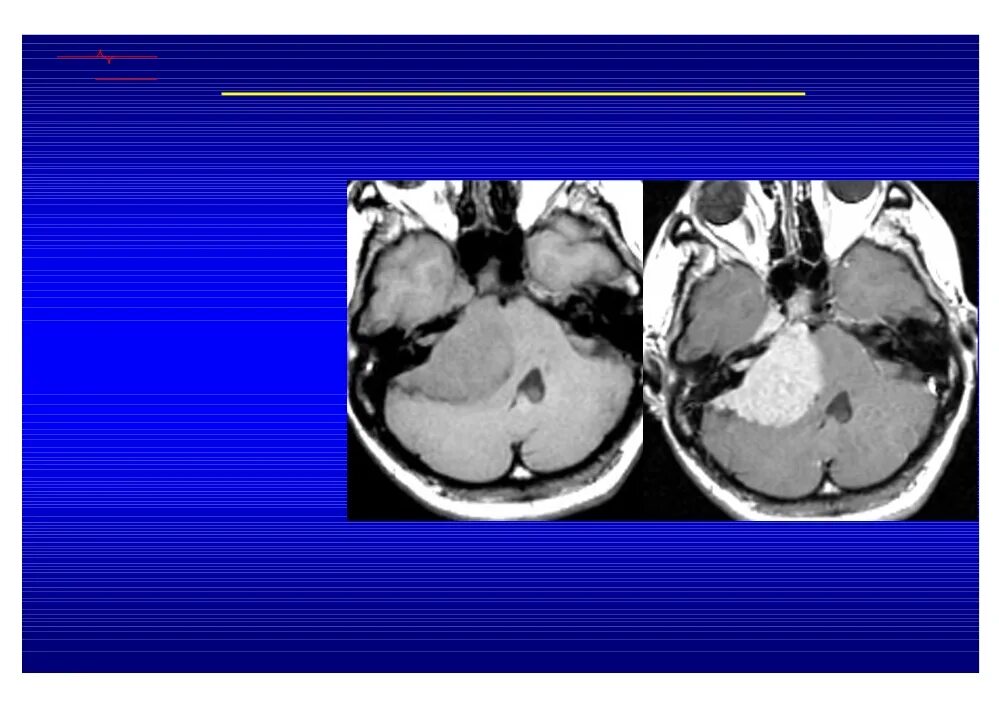

Мрт головного мозга мосто мозжечкового угла